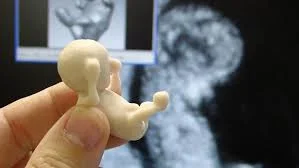

Es importante hacer mención sobre un excelente estudio Noruego donde se evaluaron 960.000 recién nacidos vivos, entre el año 1970 y 1988, con datos de peso al nacer, sexo, edad gestacional, modo de presentación y parto. Los resultados obtenidos reportaron 9.955 casos de Displasia de Cadera con una prevalencia de 1%. Para la presentación de nalgas la prevalencia fue mayor, y estaba especialmente relacionada con la edad gestacional, sexo femenino y ser el primer nacimiento. El porcentaje de Displasia de Cadera fue inferior del 0,26% en niños con peso menor de 2.500 gramos. Para la presentación de vértice o nalgas la prevalencia fue igual independientemente de si el parto fue por vía vaginal o cesárea. Por este trabajo se demuestra que el parto por vía vaginal no incremente el riesgo de Displasia de Cadera en su niño con presentación de nalgas.

Ecosonografía: Es importante tener en cuenta que no es posible diagnosticar a un porcentaje importante de Displasia Evolutiva de la Cadera con el examen físico y radiología en los dos primeros meses de vida, el Dr. Graf delineó en 1984 en Austria los diferentes aspectosecográficos de la cadera, describió una serie de ángulos medibles mediante ecografía que permiten establecer la posición de la cabeza femoral con respecto al acetábulo y la displasia presente en el mismo. Harke autor norteamericano, que destaco la importancia de un estudio dinámico del comportamiento de una cadera inestable, y la detección ecográfica de los cambios de posición de la cadera y el valor en el pronóstico y seguimiento de estos niños, este estudio es preferible al de Graft. Se debe practicar estudio ecosonográfico de las caderas ante cualquier sospecha clínica y de forma sistemática en los pacientes con signos de riesgo. La Ecografía de caderas se realiza entre el primer y segundo mes de vida (4 y 8 semanas), por lo tanto la experiencia del explorador es de vital importancia en la interpretación del examen. Sus principales ventajas es la de ser un procedimiento no invasivo, demostrándose que es el mejor método y más seguro.